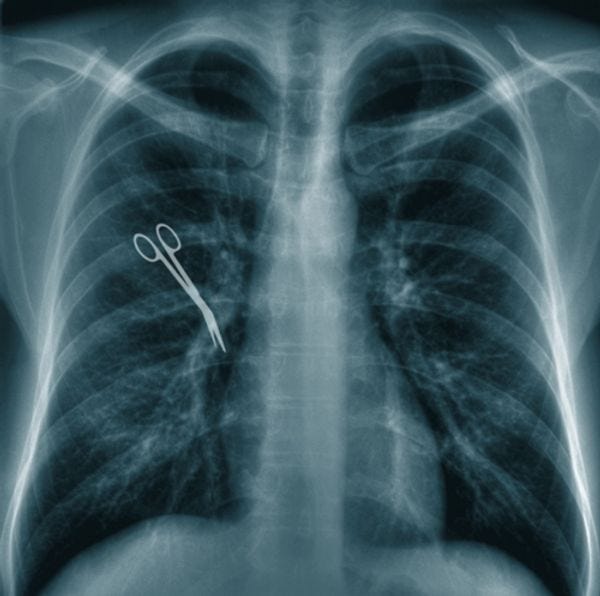

The Santorums' award check was later whittled down to $175,000, presumably by some liberal activist judge. In revenge (?), Santorum later sponsored the Healthy Mothers and Healthy Babies Access to Care Act, which would have capped awards for non-economic damages from medical malpractice at $500,000, which is all he and his family were asking for in the first place, FOR GOODNESS SAKE! Can't a guy with exceptional insurance and every possible resource in the world catch a break, ever? [ WaPo ; Image via Shutterstock ]